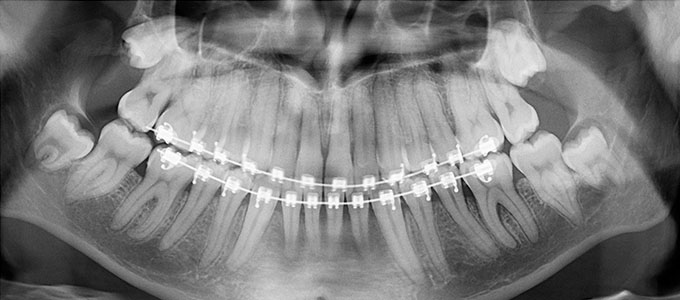

Tratamentul ortodontic este un proces biologic complex care include modificări ale oaselor maxilare, faciale și ale țesuturilor moi pe măsură ce dinții sunt mișcați în noile poziții.

Tratamentul ortodontic nu este o soluție rapidă. Acesta începe întotdeauna cu o examinare minuțioasă a dinților, a buzelor și a întregului aspect facial, sunt necesare radiografii si fotografii de diagnostic. Din aceste informații detaliate medicul ortodont dezvoltă un plan de tratament personalizat.